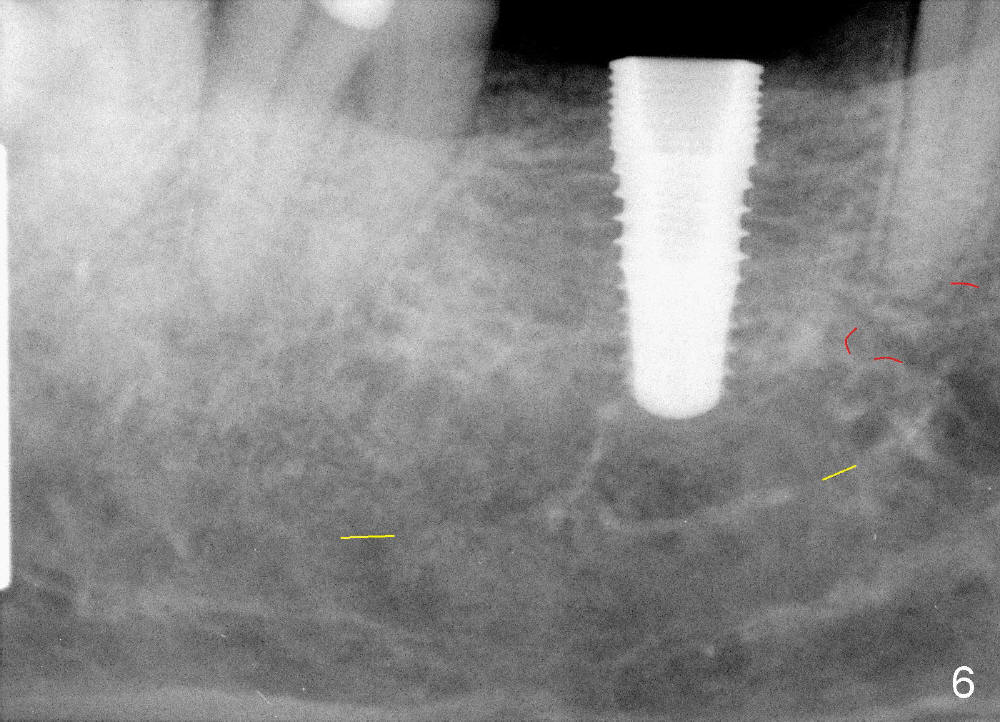

When a positioning pin is placed in the osteotomy with 10 mm deep, the sensor cannot be placed deep enough because of pin interference so no IAC is visible (Fig.4). When the pin is removed and the sensor is placed low enough, IAC is clearly shown, but the osteotomy is barely visible (Fig.5 pink dashed line). With information obtained from pre- (Fig.2,3) and intra- (Fig.4,5) op PA, twelve mm of osteotomy appears to be appropriate. A final implant (5.3x12 mm) is placed with separation from IAC (Fig.6, insertion torque 50 Ncm). A healing abutment is placed (Fig.7,8), which helps retain perio dressing (Fig.9). Two weeks later, the gingiva heals around the abutment (Fig.10). Four months postop, the implant appears to osteointegrate (Fig.11). A cemented abutment is placed (Fig.12). With supragingival margin, oral hygiene is easily maintained (Fig.13). Due to delayed placement, the gingival embrasure is extremely large (*). The issue is much less with immediate implant.